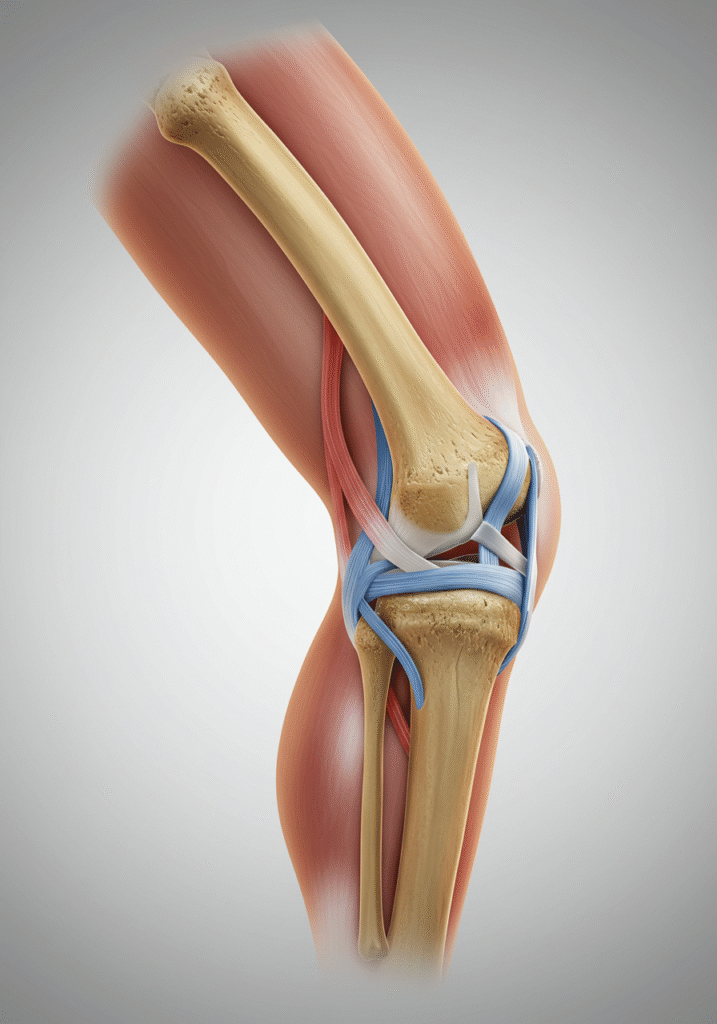

Lesión de Ligamentos de la Rodilla

¿Qué es?

Ruptura o distensión de los ligamentos cruzados o colaterales, esenciales para la estabilidad.

- Sensación de inestabilidad

- Dolor agudo tras el movimiento

- Inflamación inmediata